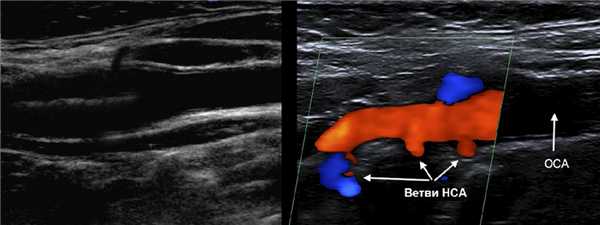

НСА начинается кнутри, затем пролегает кнаружи от ВСА; имеет короткий ствол; около угла нижней челюсти делится на восемь ветвей.

Ветви НСА: верхняя щитовидная, языковая, лицевая, восходящая глоточная, затылочная, задняя ушная, верхнечелюстная, поверхностная височная.

В В-режиме и ЦДК сканируют ОСА до бифуркации; выше бифуркации исследуют НСА через передний доступ, ВСА через боковой доступ.

У бифуркации ОСА расширение луковицы, начинается голый ствол ВСА и ветвящаяся НСА. Первая ветвь НСА — верхняя щитовидная артерия.

Отличие НСА и ВСА: на уровне бифуркации в 95% случаев НСА располагается кнутри; диаметр НСА меньше; от НСА на шее отходят мелкие ветви.